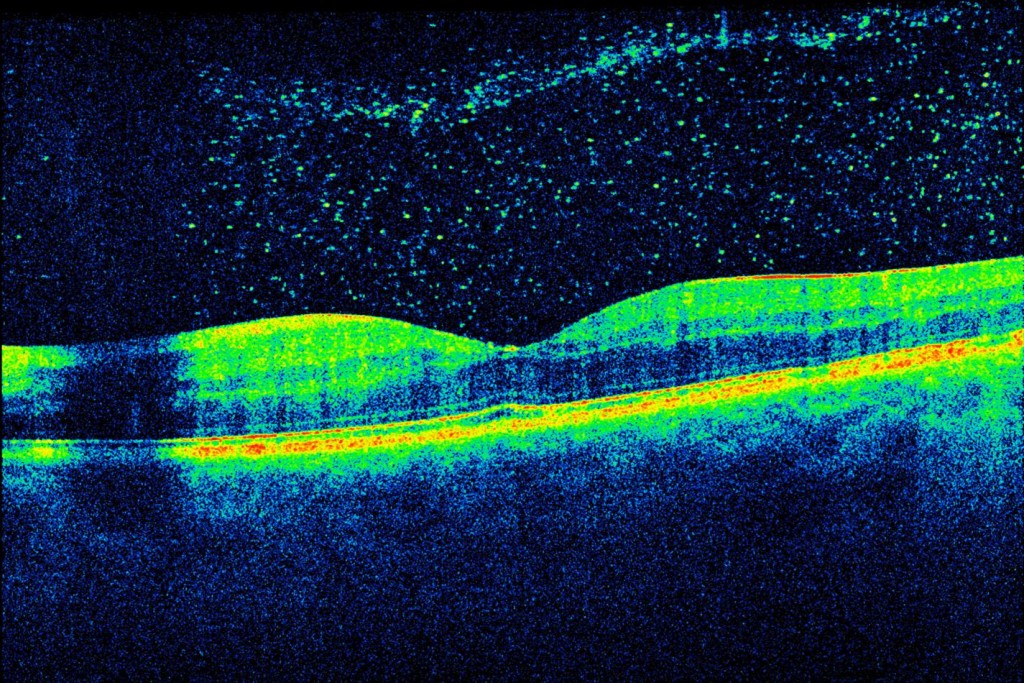

VH_OCT_edited

Full size 1425 × 950